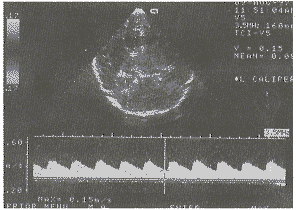

中国超声医学杂志991030 患儿男,1.5岁,不能独自站立、不会走。查体:神志清,智力反应差。背部有一1cm×1cm淡红色斑痣,面部无皮损。四肢活动不灵活,肌张力增高,膝反射活跃。超声检查:(前囟窗)脑中线居中,双侧侧脑室对称,前角扩大、变钝,宽1.1cm,脑中线到前角处侧壁距离2.4cm。颅组织回声均质。双侧侧脑室下方见一5.7cm×7.5cm×5.2cm圆形强回声光团,中心回声稍低。其内有不规则“小等号”状血管断面回声。边缘清晰,有线状高回声。不伴声影和声晕,后方无衰减(见图1)。彩色多普勒超声显示:内部及周边少许点状及斑片状色彩暗淡的血流信号。脉冲多普勒在肿物周边探及低速动静脉血流信号(见图2)。双侧大脑中动脉、左侧大脑前及大脑后动脉血流速度明显增高,收缩期、舒张期均增高。频谱形态正常,PI、RI、S/D正常。右侧大脑后动脉正常。未探及右侧大脑前动脉。超声诊断:颅内血管瘤。MRI证实为颅内巨大血管瘤。

图2 血管瘤周边动脉血流频谱